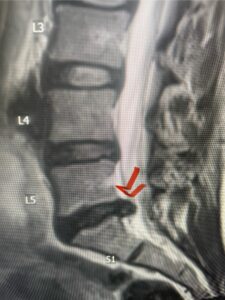

In this next case, this patient is a 47 year-old female who presents with intractable low back pain with severe pain, numbness, and weakness in the right lower extremity that had gotten progressively worse over a year. The patient had failed conservative management including physical therapy and epidurals. She was noted to have ⅘ weakness of plantar flexion. MRI demonstrated a large right L5-S1 disc herniation with severe compression of the descending right S1 nerve root (Fig 3). It was decided to perform a right L5-S1 hemilaminectomy for removal of the disc fragment and decompress the S1 nerve root. When you expose the disc, one must be certain to release any anterior adhesions to the nerve root in order to prevent a dural tear during retraction of the nerve root. It is also important to make sure during exposure and you finally encounter the dura after removing the ligamentum and fat, to make sure you are looking at the nerve root and not the main trunk of the thecal sac because if you don’t you can avulse or damage the nerve root if you retract the wrong structure.

Fig. 3a: Sagittal and axial T2-weighted lumbar MRI images demonstrating large right L5-S1 disc herniation (red arrows)

We found a massive subligamentous herniation which had to be revealed by having your partner retract the freed nerve root with a nerve root retractor and putting slight downward pressure on the more medial and anterior disc space. There is nothing more satisfying when the jelly (disc fragment) of the annulus (donut) comes squirting out and you remove a large chunk of disc material that clearly was stretching the ligament membrane and compressing the nerve root. This does cause back pain in addition to radiculopathy not only by the component of mechanical compression but also the stretching of the nerves within the ligament. We performed this surgery and noted that the nerve root was a very angry red color or hyperemic and we removed a large subligamentous fragment. The patient had improvement of her preoperative radicular symptoms.